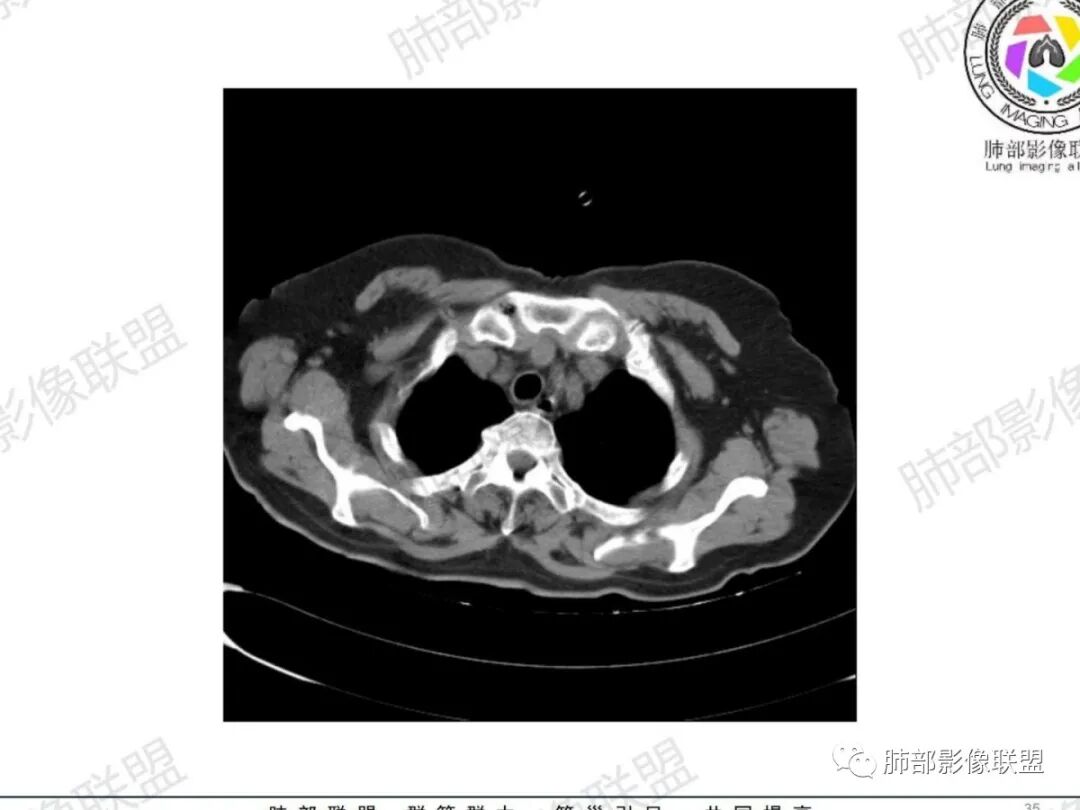

主支气管后缘外可见一实性结节,病变跨支气管管壁生长,部分突向管腔内,病变边缘光滑,平扫密度均匀,增强后尚均匀强化,纵隔淋巴结肿大不明显。

气管右后侧壁结节,结节向气管腔内突出,气管壁增厚,轻度强化,左侧甲状腺占位,考虑气管原发肿瘤,腺样囊性癌?类癌?

气管右后壁占位,平扫密度稍低于肌肉

增强后与肌肉类似,部分强于肌肉,提示强化

内外边缘光滑

宽基底与气管相连

附近壁增厚

前方见一小淋巴结,后内侧与食道联系很紧